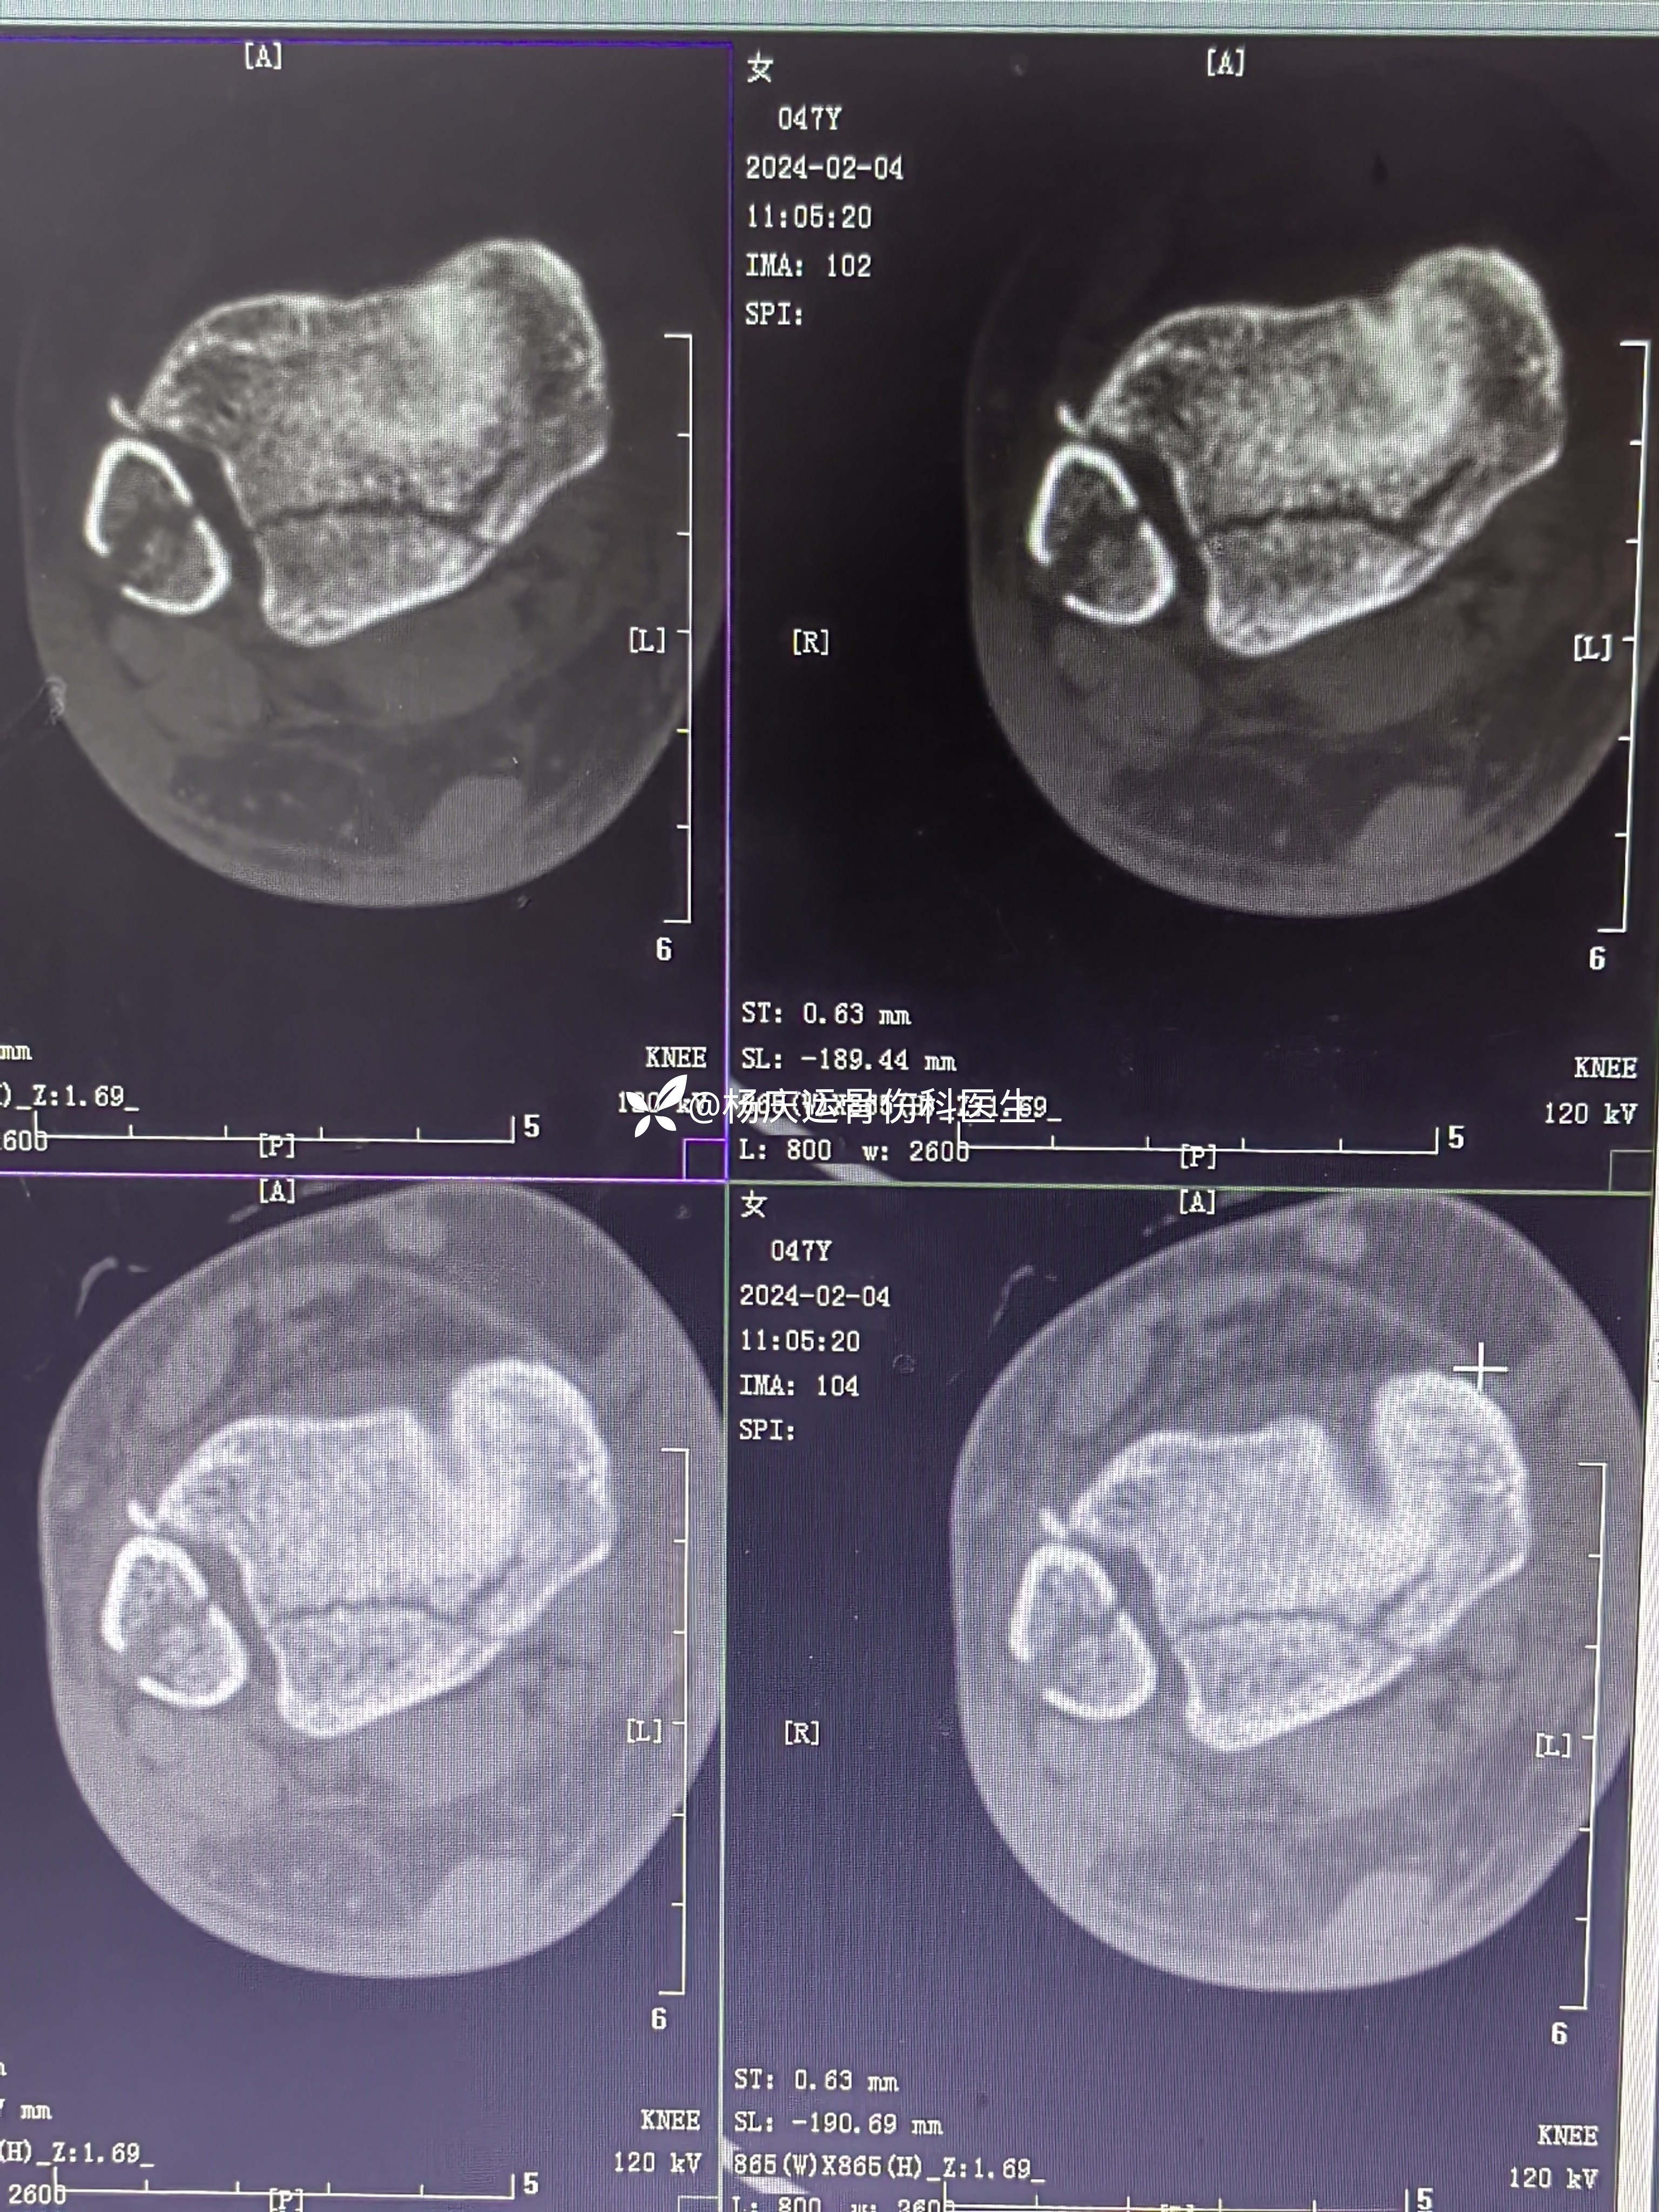

首诊三维CT

3天复查CT

关节面台阶约1.0mm